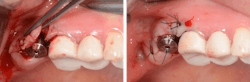

As the landscape of implantology evolves, the adoption of hydraulic lifts is poised to become the gold standard in noninvasive sinus lift surgeries, reshaping the future of dental implant procedures (figures 4–11).